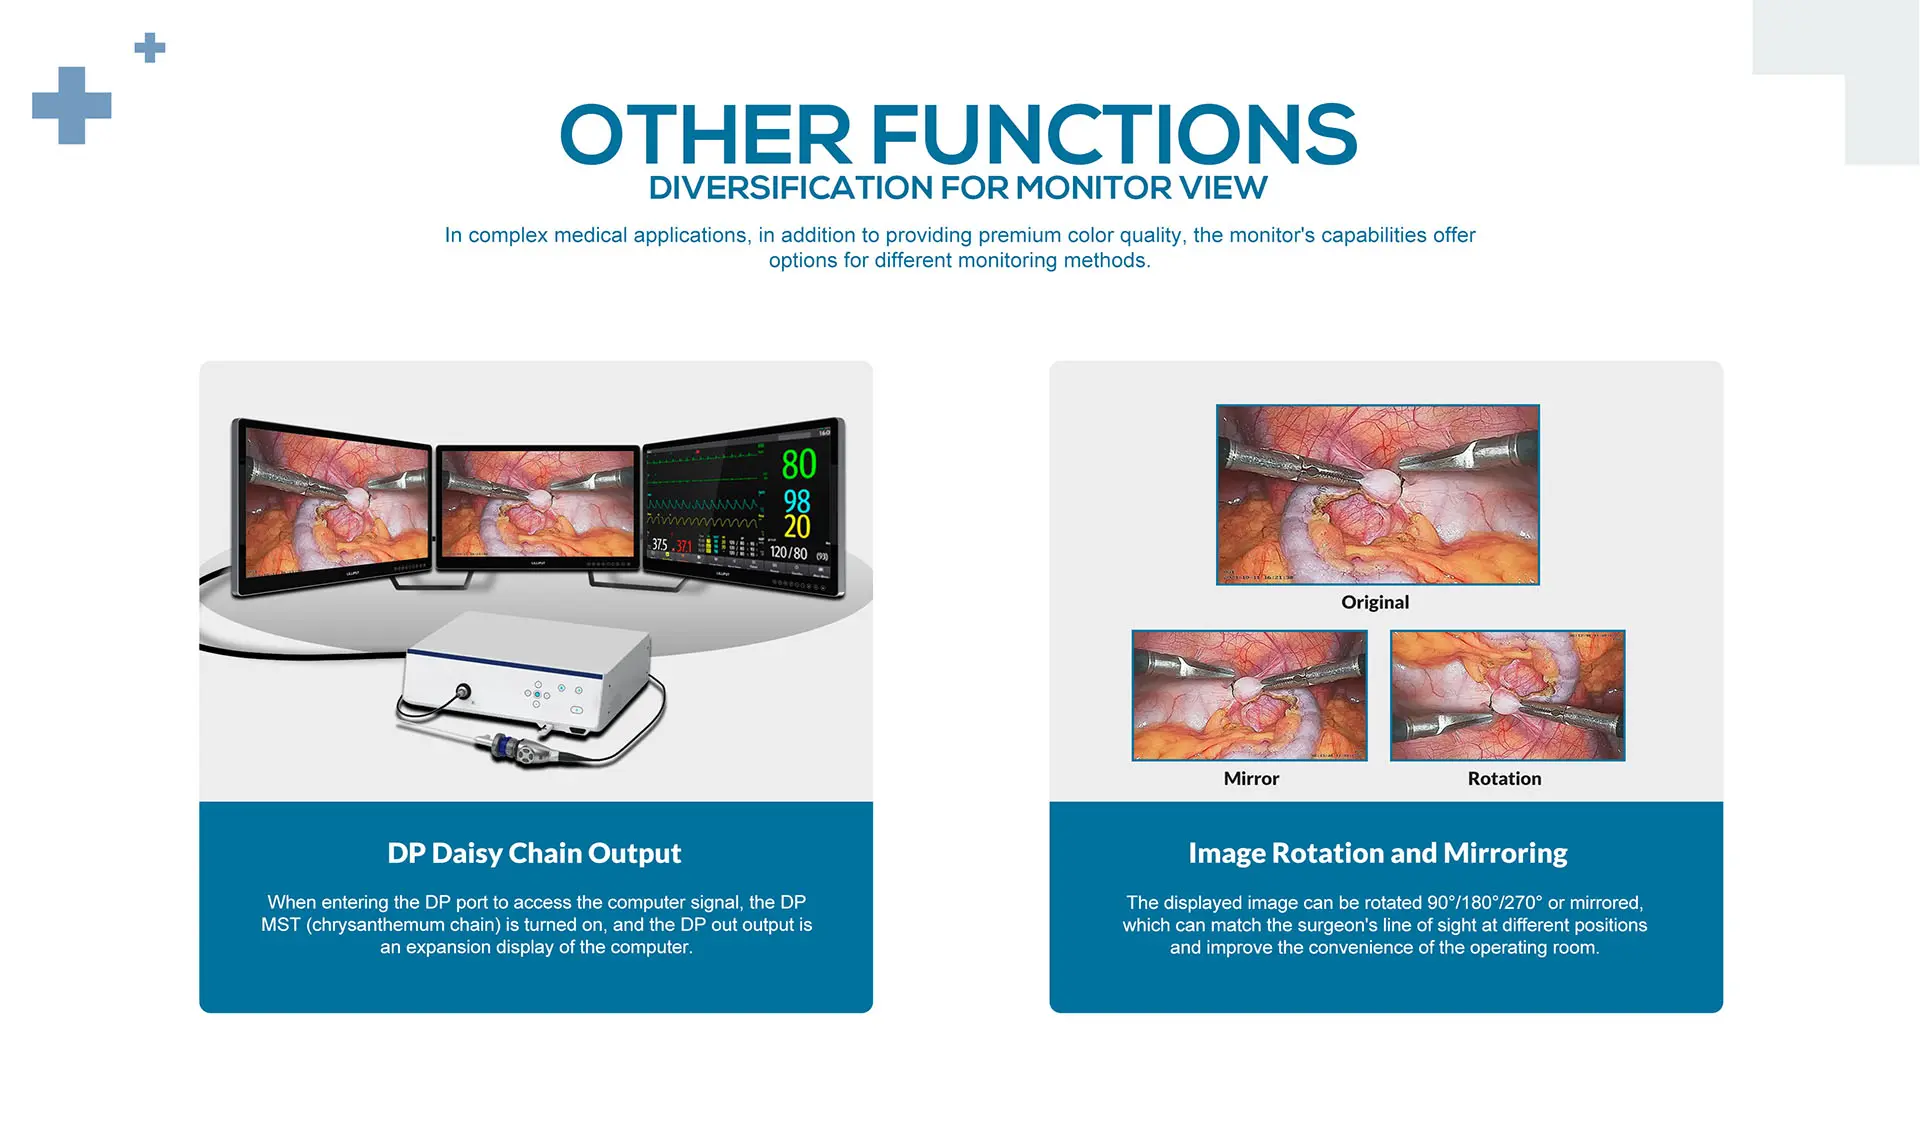

- DP daisy chain output

- Support image rotation and mirroring